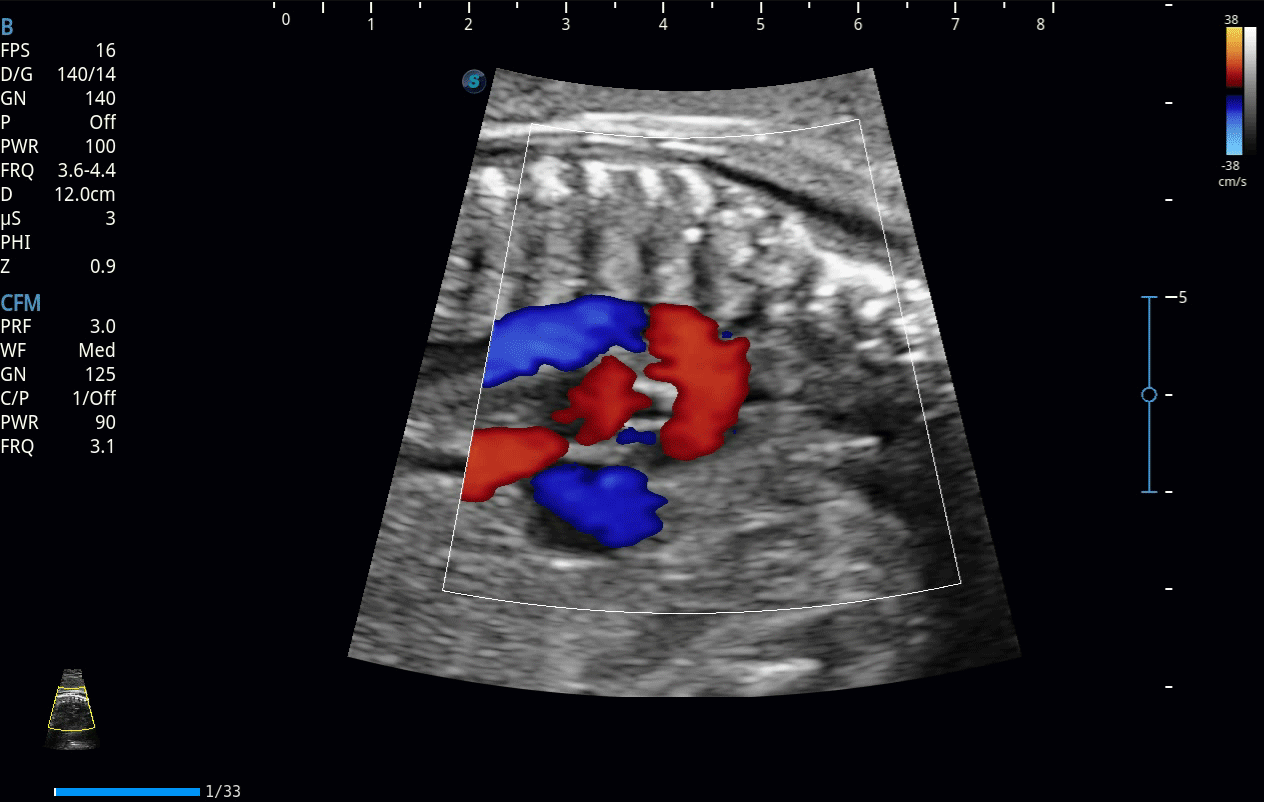

開立醫(yī)療通過不斷的技術(shù)創(chuàng)新,為大眾的生命健康提供持續(xù)關(guān)愛。P12 Plus采用全新一代超聲成像平臺,新平臺旨在將真實(shí)還原組織解剖結(jié)構(gòu)作為首要目標(biāo)。平臺采用全新集成化硬件模塊,搭載新一代芯片,系統(tǒng)性能得到大幅提升,為您的診斷提供了豐富的臨床信息。優(yōu)異的圖像表現(xiàn),豐富的探頭配置,全面的應(yīng)用功能,為您日常診斷提供了可靠的助手。

彩色多普勒超聲診斷系統(tǒng)